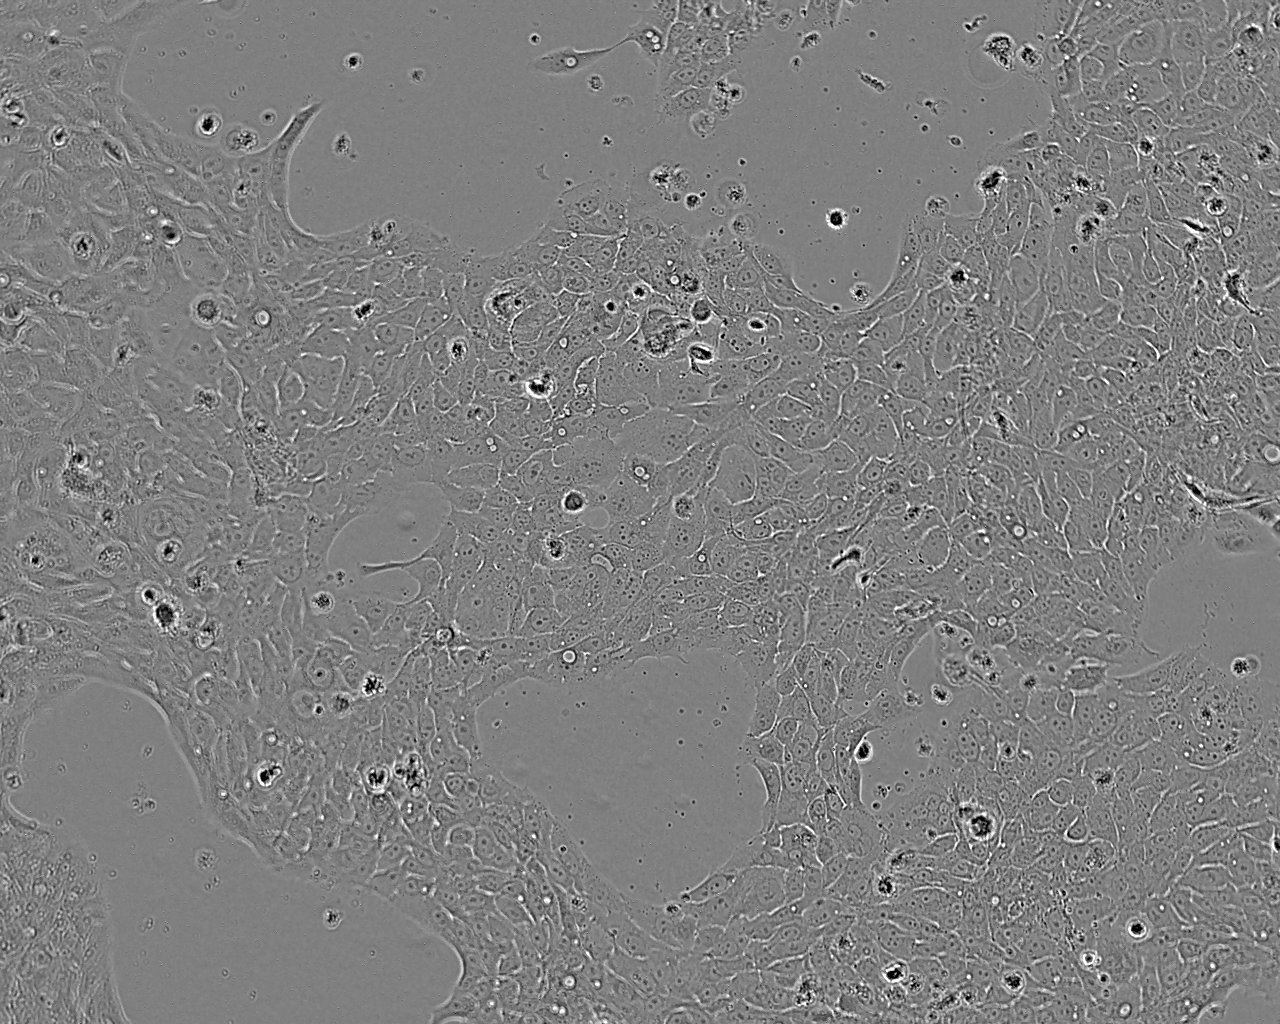

Images

Split sub-confluent cultures (70-80%) 1:4 to 1:10 i.e. seeding at 1-3 x 10,000 cells/cm² using 0.05% trypsin or trypsin/EDTA; 5% CO₂; 37°C. Population doubling approx 44hrs.

Growth Mode